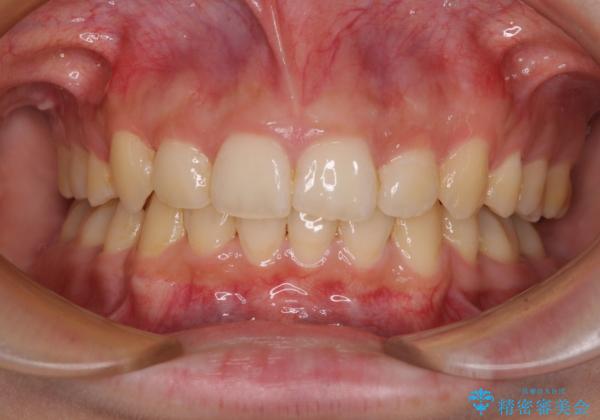

下顎前歯が隠れて突出した口元 ワイヤー装置での抜歯矯正

- 前歯のデコボコと口元の突出感を気にして来院された患者様です。

下顎骨の左右差や、上顎骨の前方位などが認められたため、上下左右の第1小臼歯4本を抜歯し、ワイヤー装置にて矯正治療を行うこととしました。

骨格的な左右差がありましたが、何とか当初予定していた期間で、左右対称の咬み合わせに仕上げることができました。